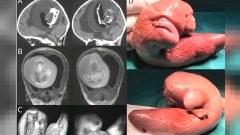

ตะลึง!! พบแฝดน้องในหัวของแฝดพี่